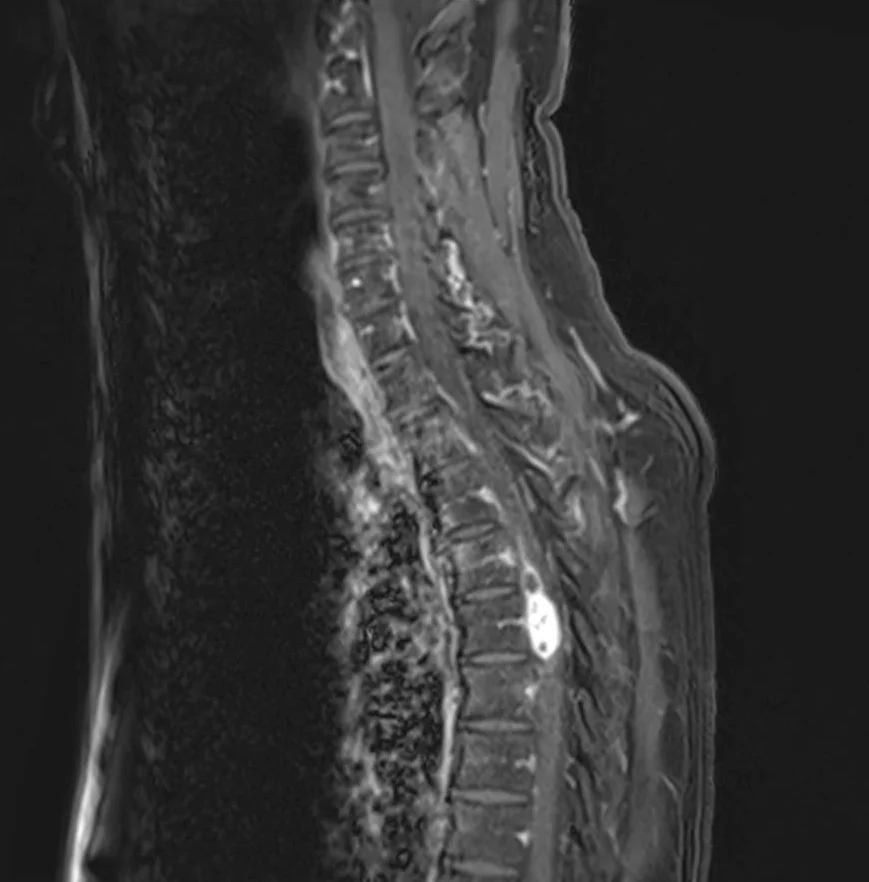

Le diagnostic est fait classiquement sur l’ IRM de la moelle épinière avec injection de Gadolinium. En fonction de la localisation et de l’aspect de la tumeur, votre neurochirurgien pourra vous demander de compléter ce bilan par un scanner et/ou une artériographie médullaire, qui pourra être organisée dans le service de Neuroradiologie interventionnelle situé dans le bâtiment Babinski (Pr Clarençon).